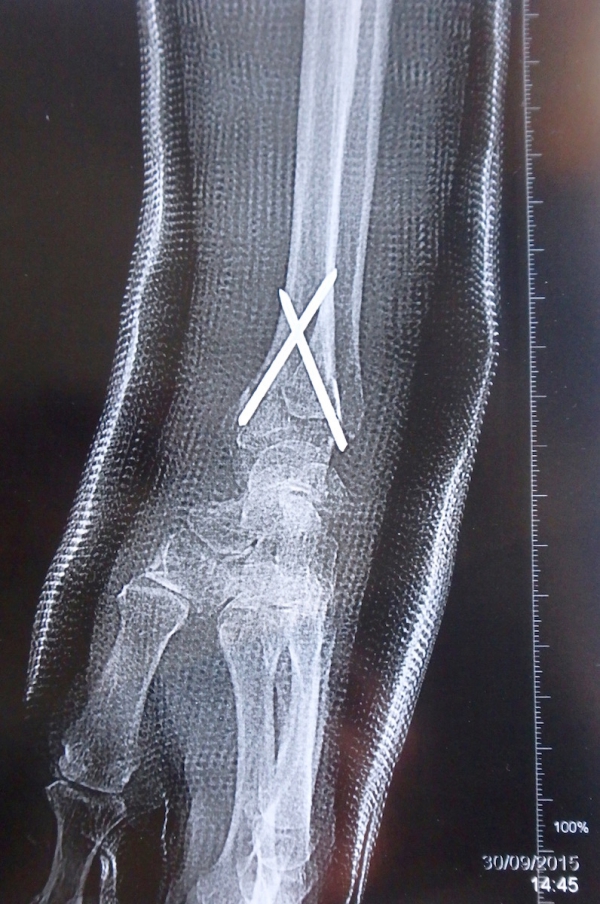

Radio du poignet de Simone le jour de son opération. On voit clairement les deux broches (Clinique de l’Europe, mercredi 30 septembre 2015).